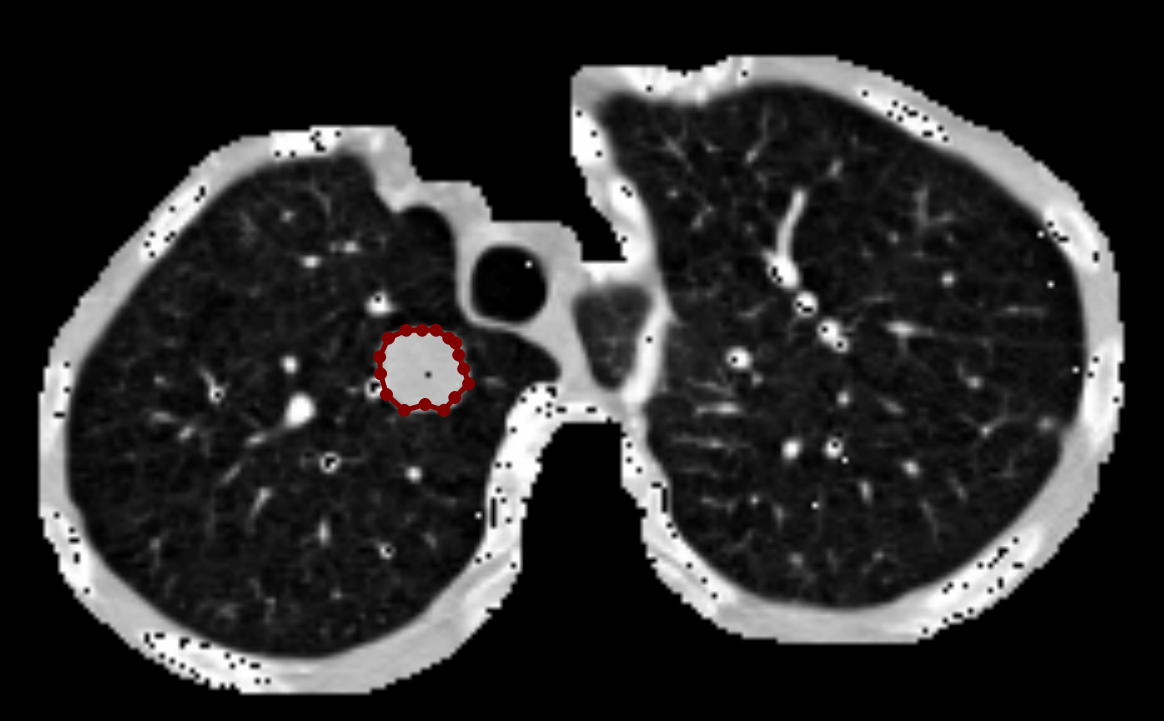

具体而言,本文以目标检测结果中的边界框为参考,结合原始 CT 图像内容,使用 LabelMe 软件对每一个肺结节区域进行逐个手动标注,精确描绘其轮廓,生成对应的 JSON 格式标注文件。每个 JSON 文件中包含了结节边界的多边形坐标信息,可用于自动生成二值掩膜图或直接用于实例分割模型训练。

如下图所示,在每张图像中,我们严格遵循每个结节的实际形态进行轮廓描绘,确保掩膜区域与实际病灶最大程度吻合。这种高质量的人工标注为分割模型提供了可靠的监督信号,有助于提升模型对细小或边缘模糊结节的识别能力。